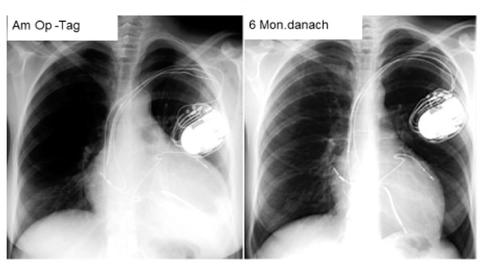

© herzmedizin.berlin Schrittmacher zur Behandlung einer Herzschwäche: Herzvergrößerung als Zeichen einer Herzschwäche (linke Abbildung). Deutliche Herzverkleinerung als Zeichen der Herzkräftigung (rechte Abbildung).